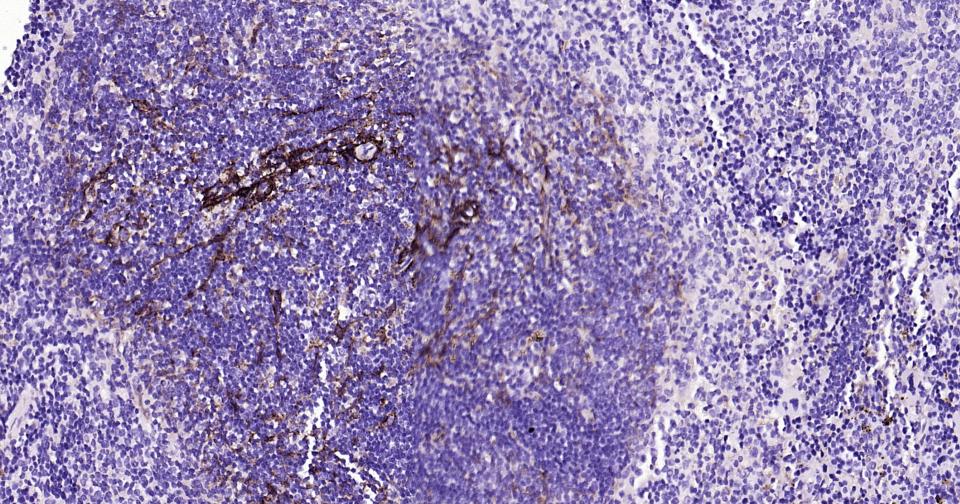

IHC-PHuman, Mouse, Rat1:100-500

IHC-FHuman, Mouse, Rat1:100-500

IFHuman, Mouse, Rat1:100-500

ICC/IFRatHuman, Mouse1:50-200